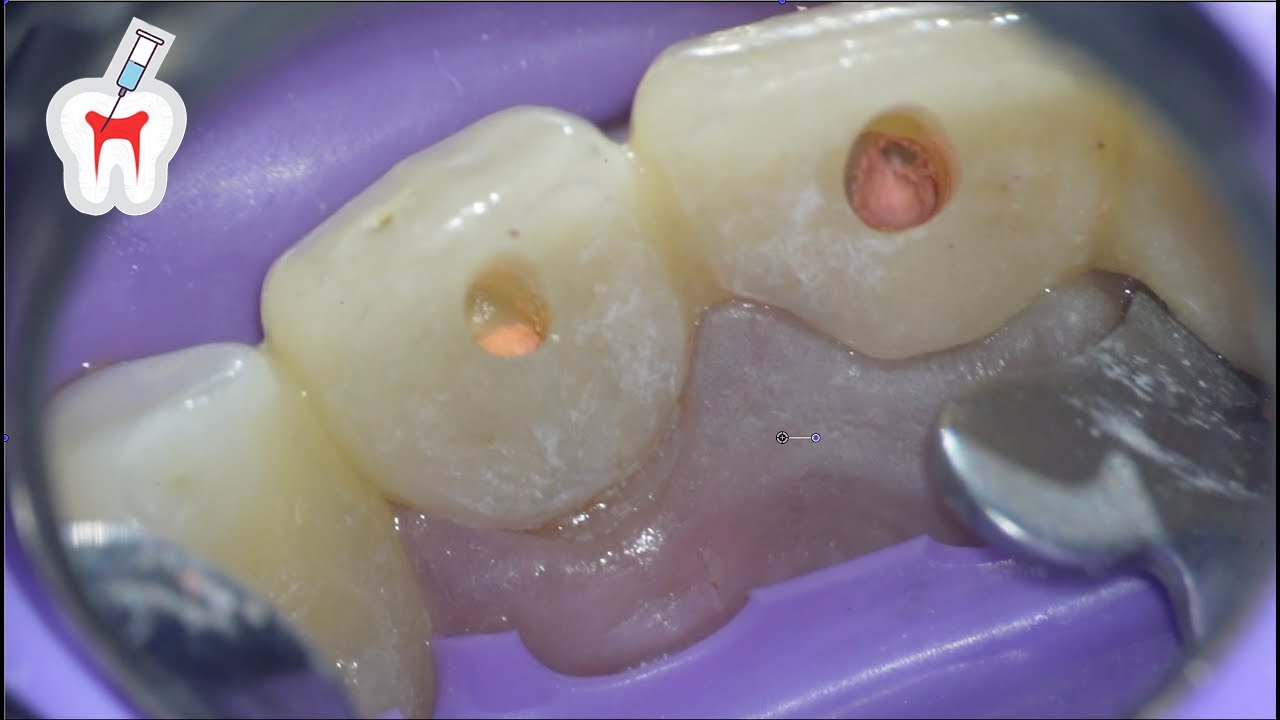

Anterior Root Canal Procedure 2 Upper Centrals Retreatment YouTube Anterior Root Canal Treatment Video A root canal is necessary when. An informational video explaining the step by step processes that are involved when endodontically treating your teeth. Live root canal (endodontic) treatment on tooth #18 performed by dr. Yocasta caba shares this animation of a root canal treatment. Want to know more about root canal (endodontic) treatment? This 3d medical animation features a procedure. Anterior Root Canal Treatment Video.

From www.youtube.com